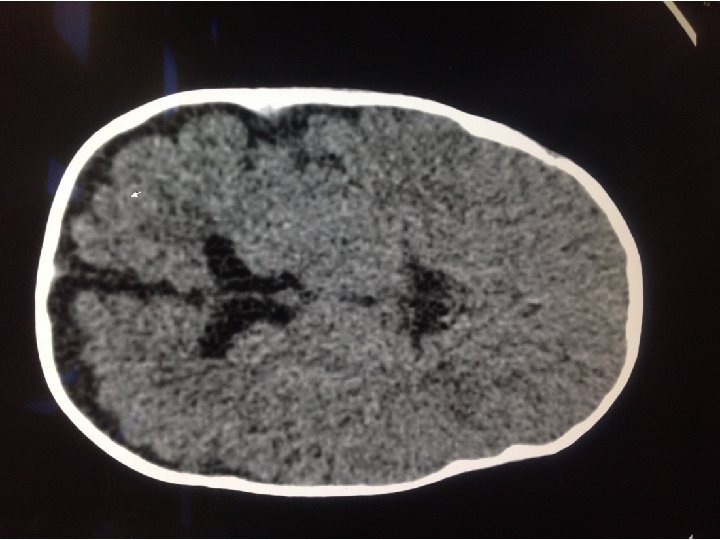

WORK UP • Basic labs • CBC, CMP, PT, INR, PTT • CT Head

SOOOO…. . ? • CT shows scaphocephaly, but normal ventricles. • No acute neurosurgical concerns • Primarily sent for nystagmus • Could the nystagmus be anything else?